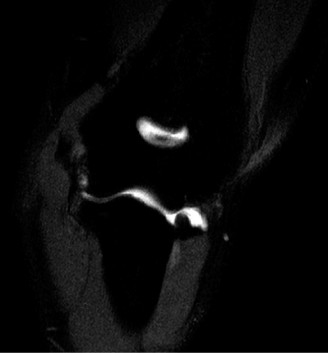

Identify the muscles that compose the force couples in the transverse and coronal planes? CASE 3 A 35-year-old male has had left shoulder pain for 4 months, ever since a low-speed motor vehicle accident (MVA). Physical examination demonstrates preserved range of motion but pain and some weakness with Jobe’s testing. His imaging is shown in Figure 2–8.

Figure 2–8_Reproduced with permission from Stadnick ME. _Partial Rotator Cuff Tears. MRI Web Clinic. 2007 (Apr).

What is the most likely diagnosis?

The correct answer is (A). These are best diagnosed on an MRI as seen in the imaging provided; addition of intra-articular contrast can further improve this study. Answer B, full-thickness rotator cuff tear, is incorrect as the bursal side of the tendon can be seen to be in continuity. Answer C, a SLAP lesion, will be visualized as a labral tear on a coronal MRI and will be found at the biceps root. Answer D, an ALPSA lesion, will be most clearly seen on an axial MRI. It is a variant of a Bankart lesion where the labrum is displaced medially and inferiorly rolling down the glenoid neck underneath the periosteum.

MRI remains the most popular imaging modality for diagnosing rotator cuff tears. Normal rotator cuff tendon appears dark on both T1 and T2 sequences. Tears may be noted as being full-thickness, articular-sided, bursal-sided, or intrasubstance. They are visualized as a disruption in the regular contour of the tendon and increased signal intensity on T2 sequences. Occasionally, an MR arthrogram may provide additional information regarding a cuff tear, although this is not routinely ordered.